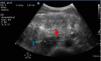

Se realiza ecografía de abdomen (fig. 1) en la que se objetiva inflamación de la pared del intestino grueso (flecha roja) con un grosor de 1,45cm (valor normal 0,3cm) y ausencia de peristaltismo visualizado en vídeo en comparación con el asa de intestino delgado (flecha azul), hallazgos compatibles con colitis que posteriormente se confirma por TC (fig. 2).